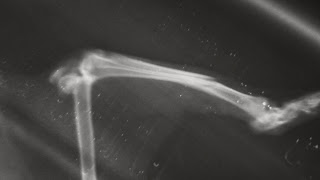

Ela vinha desnutrida, com uma pata totalmente atrofiada e cheia de pus. Pensava-se que seria uma gata adulta já com a sua idade, mas depois de tirados os raio-X, viu-se a linha de crescimento dos ossos, e um facto ainda mais arrepiante… Esta Cinza, tem ossinhos frágeis, tão frágeis que uma operação para recuperar uma das suas DUAS fracturas iria fazer com que os grampos estalassem o osso. Ela tinha passado fome, durante quase todos os seus meses de vida, nunca teve uma alimentação adequada.

Mas nem tudo podem ser más notícias, esta pequena gata (quase do mesmo tamanho do nosso Amiss de 3 meses) ainda é jovem, e as perspectivas para a recuperação da pata são promissoras. Assim que totalmente recuperada da infecção e com um peso razoável, esta gatinha será sujeita à esterilização, a anestesia será aproveitada para fazer uma reconstrução do tendão de Aquiles que foi rompido. Depois disso seguir-se-á um tempo em que precisará de todo o apoio e o espaço de um lar para poder recuperar a força muscular perdida.